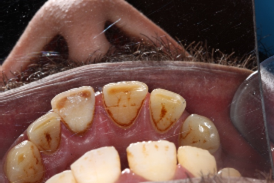

Dental trauma management

Pre-operative photo and X-ray

6 month review